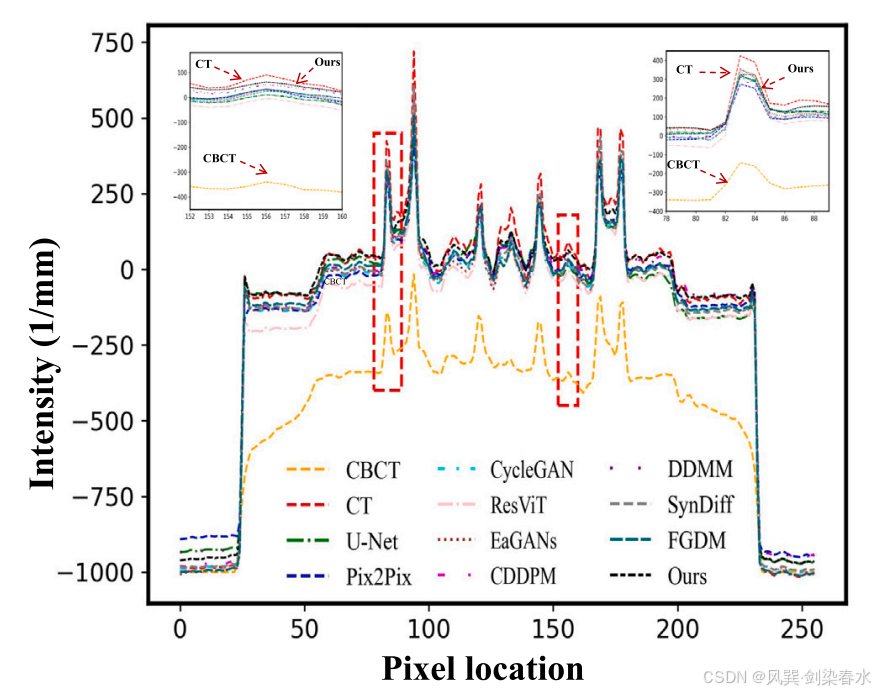

Figure 3 | 图2 所示的一维强度分布是通过沿红色虚线扫描得到的:图中的插图清楚地显示了与其它方法相比,所提出的方法具有优越的性能: